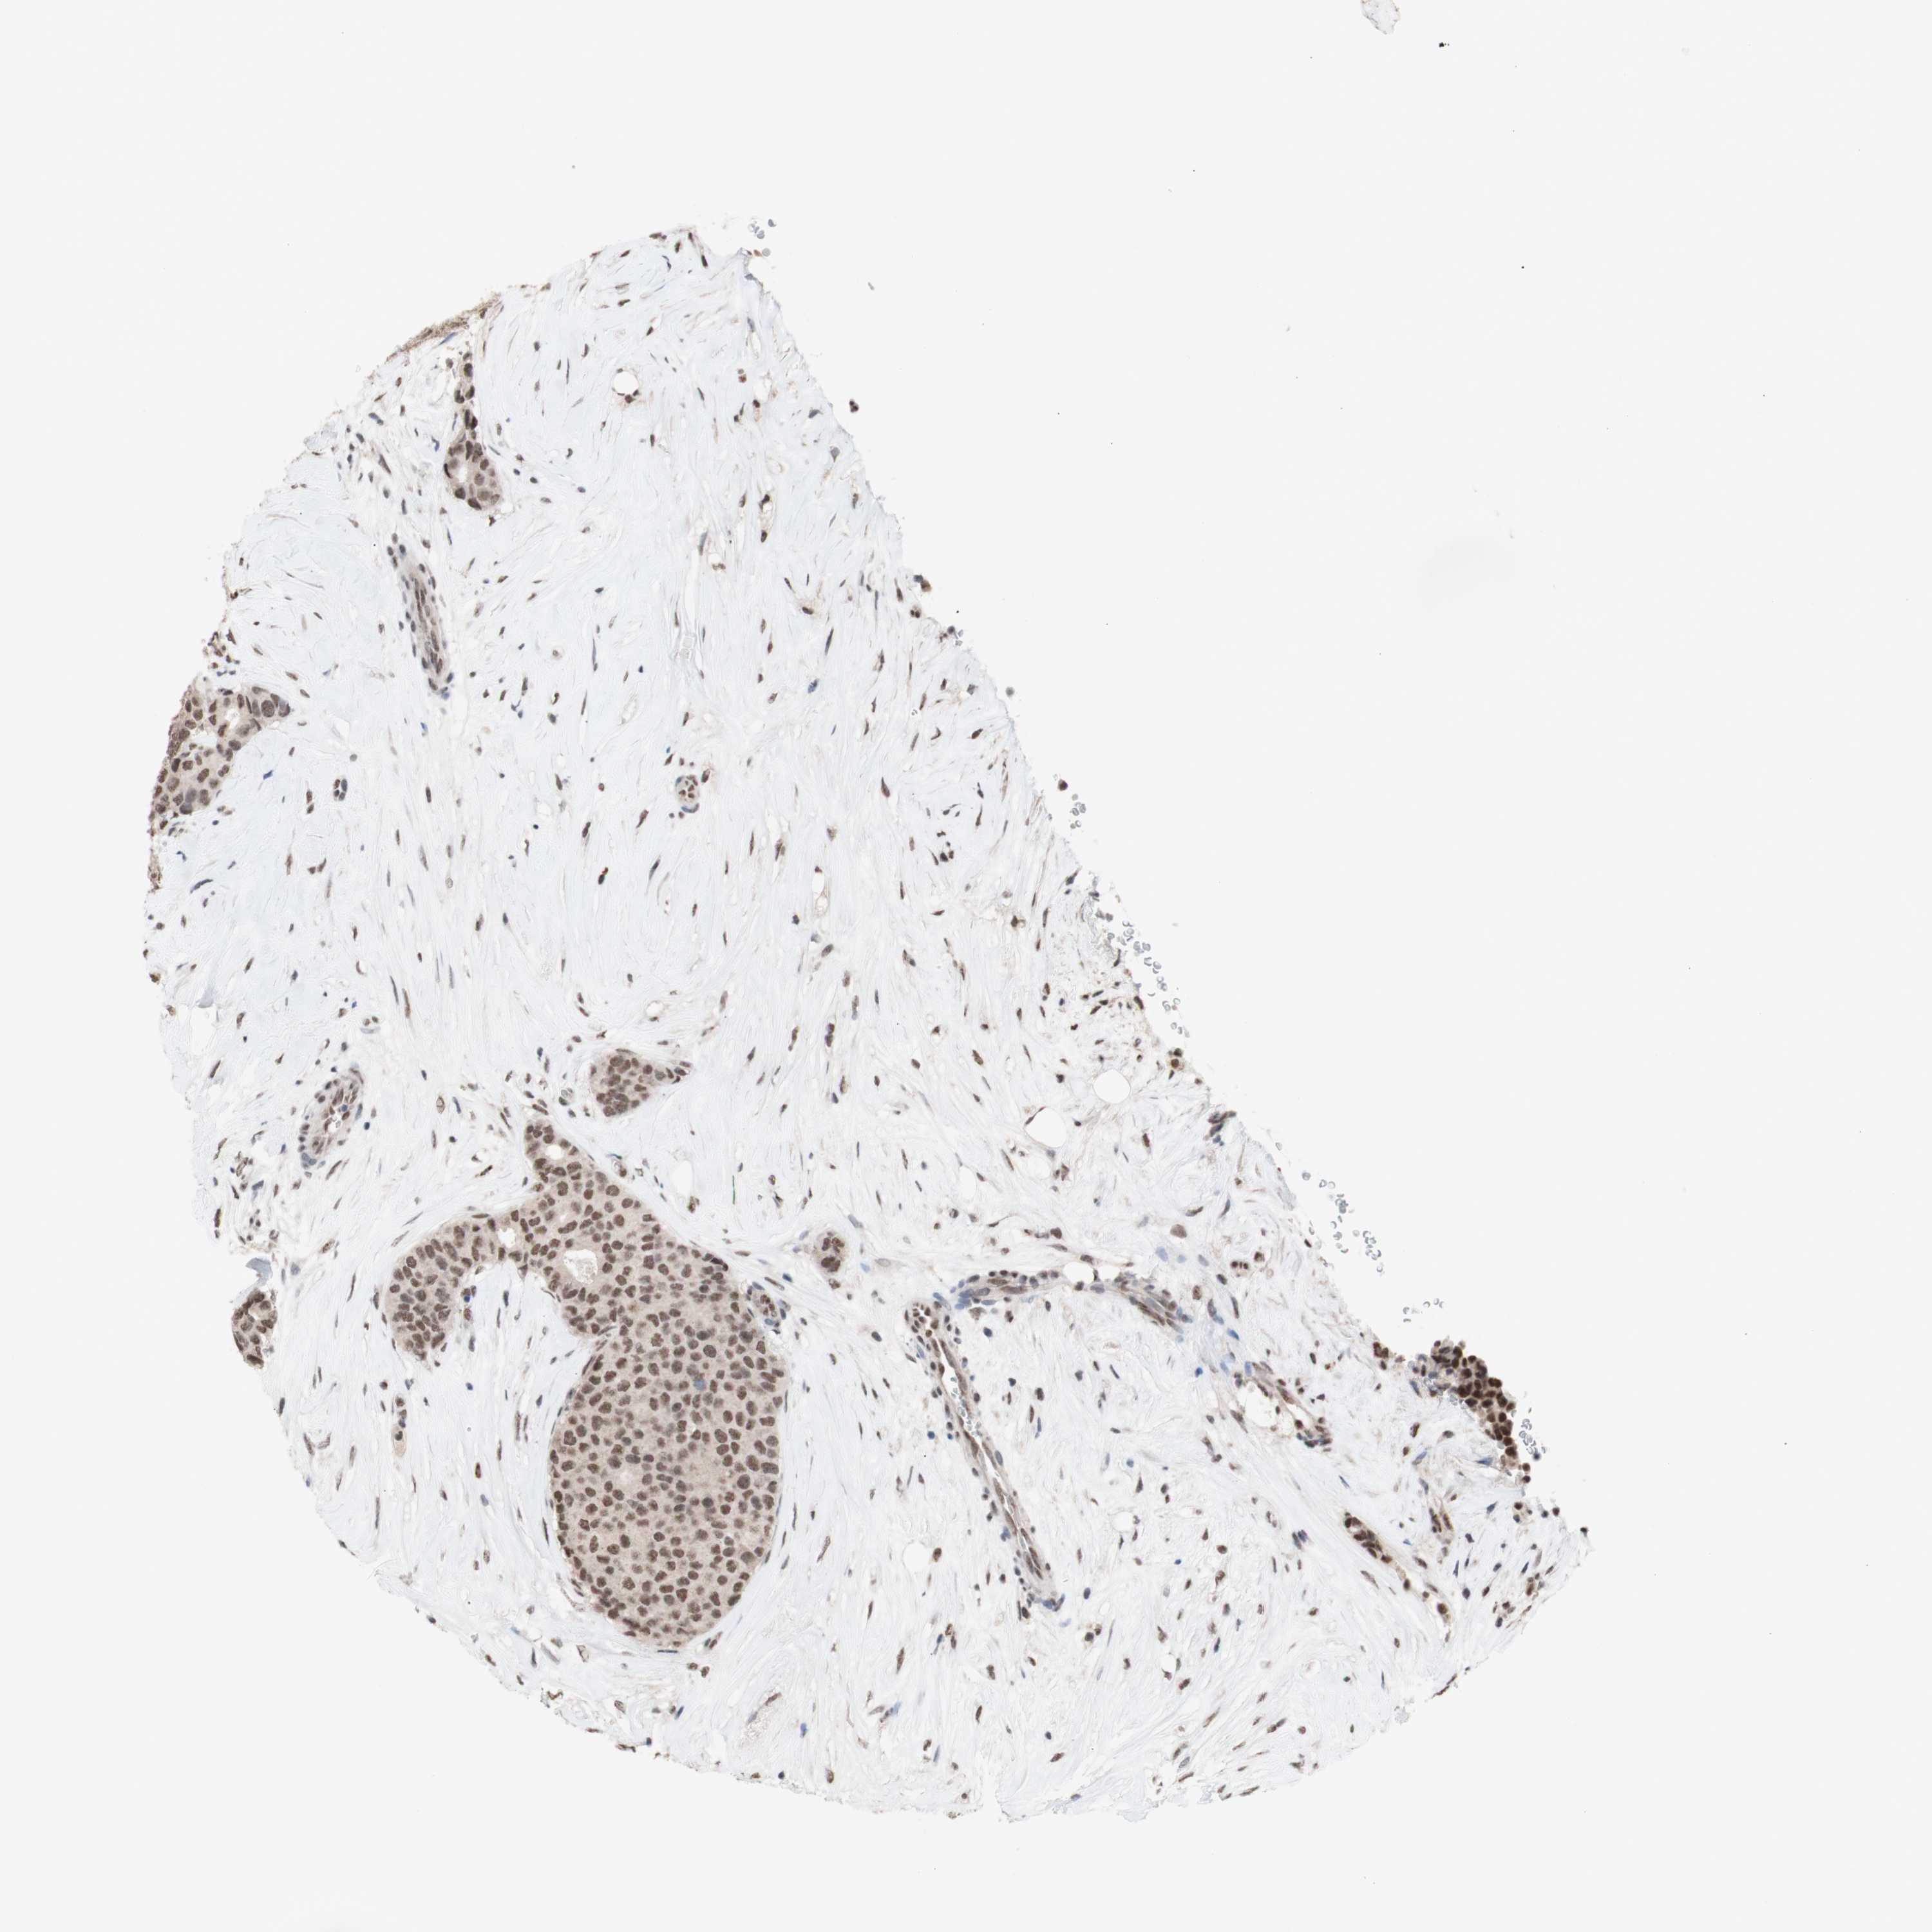

CANCER BREAST CANCER Show tissue menu

BRCA TCGA BRCA VALIDATION PROTEIN EXPRESSION

ANTIBODIES

AND

VALIDATION